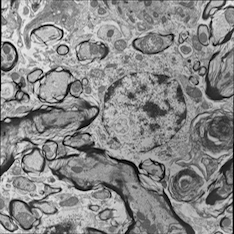

For image analogies based image registration, I have corresponding TEM/Confocal Microscopic image pairs of mouse brains with corresponding regions highlighted by a box. Using the correlative microscopy technique on the mouse brain, I want to localize specific brain regions associated with Pelizaeus-Merzbacher Disease (PMD) and do quantitative assessment of hypomyelination and demyelination in mice. PMD is one of a group of genetic disorders characterized by progressive degeneration of the white matter of the brain affecting the myelin sheath, the fatty covering that acts as an insulator on nerve fibers in the central nervous system.

The confocal microscopy images are multichannel color images in our test dataset. The blue channel is based on the blue stain DAPI (a fluorescent stain) which stains the DNA of the cell nucleus and corresponds to dark regions within the nuclei in the TEM. The green channel is based on the stains of the myelin sheats, visible as dark black layers covering the neurons in the TEM images. The red channel is not explicitly stained for and is caused by the auto-fluorescent effect of lipofuscin. The confocal image with RGB channels and its corresponding TEM image are shown in Fig. 5.

Currently I have six pairs of 2D TEM/confocal images with resolutions 582.24 pixels per μm𝜇𝑚\mu m and 7.5887.5887.588 pixels per μm𝜇𝑚\mu m respectively (1μm=1micron=106m1𝜇𝑚1𝑚𝑖𝑐𝑟𝑜𝑛superscript106𝑚1\,\mu m=1\,micron=10^{-6}\,m). The resolution is different between two images and only a small region in the confocal image corresponds to the TEM image.

Refer to caption

(a) Red channel of confocal image

(b) Green channel of confocal image

(c) Blue channel of confocal image

(d) Grayscale of confocal image

(e) Confocal image

(f) TEM image

Figure 5: Example of Confocal image with RGB channels and TEM image